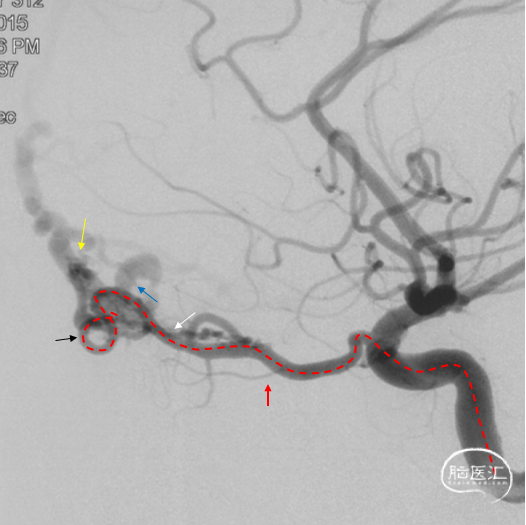

通过Marathon微导管注入Onyx 18,胶向瘘口弥散,并弥散至镰前动脉。

停顿后进一步注射Onyx18,此时胶向对侧筛前动脉弥散,直至闭塞瘘口和引流静脉起始端。

最终造影瘘口完全不显影。

双侧脉络膜染色正常。

Onyx胶铸型进一步显示了瘘的结构。AFA:镰前动脉;AEA:筛前动脉;PEA:筛后动脉;DV:引流静脉。

术后三个月造影复查,双侧颈内动脉、颈外动脉造影均未见静脉早显,DAVF治愈。